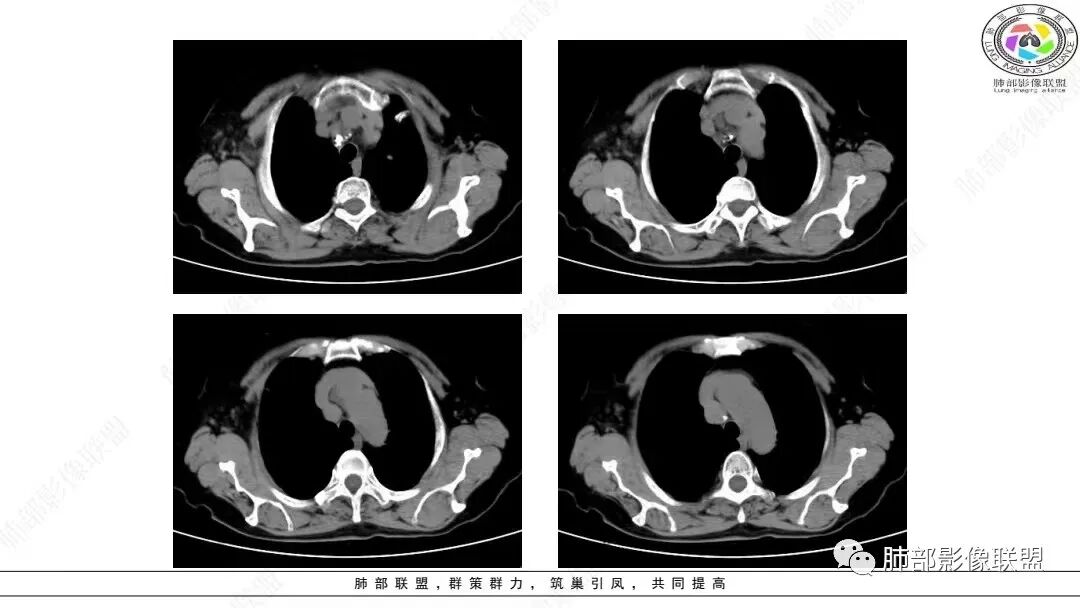

2.影像学特点:右肺上叶前段胸膜下不规则较大团块影,边界清楚欠光整,浅分叶,肺血管支气管出入,边缘膨隆胸膜凹陷具有一定张力,未见典型粗短毛刺,部分围以边界清楚的磨玻璃影,灶周小叶间隔增厚。块影密度不均,渐进性强化,可见砂砾样钙化,未见明显液化坏死或空洞。增强后病灶显示渐进性强化。MIP显示病灶内肺动脉穿行、并部分肺动脉受侵变细。纵隔及右锁骨上(胸廓入口)见肿大淋巴结。两肺可见多发大小不一的结节影,边界清楚,随机分布。

本组97.13%病变累及胸膜,大部分病灶(75.41%)与纵隔关系密切,表现为靠近肺门或紧贴纵隔胸膜生长,多数病灶与纵隔胸膜之间有脂肪间隙存在。    111例(111/244,45.49%)显示“类胸膜尾征”改变,即肿瘤紧贴胸膜生长、增厚,但未突破胸膜向外生长,与正常胸膜的夹角呈钝角,在纵隔窗上呈现类似脑膜瘤的脑膜尾征样改变;推测其形成机制可能是肺LELC的生物学行为具有一定恶性,易侵犯胸膜,使胸膜增厚逐渐延伸,但其恶性度低于肺鳞癌、腺癌,较少直接导致胸膜不均匀增厚甚或突破胸膜向外生长。

本组50.82%(124/244)病灶周围见磨玻璃密度影改变,33.20%在磨玻璃密度影中伴有小叶间隔的间质增厚,表现为小叶间隔网格状增粗,但不伴有串珠状排列的小结节;其形成机制可能是肿瘤周围实质及间质均伴有大量淋巴细胞浸润以及小叶间隔的淋巴管扩张,而肺腺癌或鳞癌的癌性淋巴管炎多表现为小叶间隔结节状增厚,可呈串珠状改变。上述征象可作为肺LELC与肺鳞、腺癌的鉴别点。